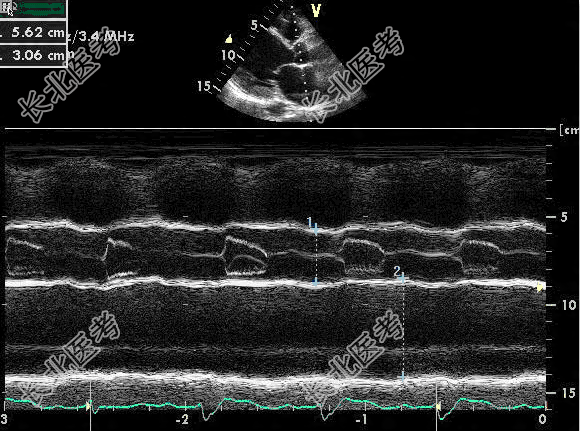

- 单项选择题M型超声心动图如图,正常成人主动脉瓣开放幅度应不小于

A、10mm

B、30mm

C、18mm

D、20mm

E、16mm